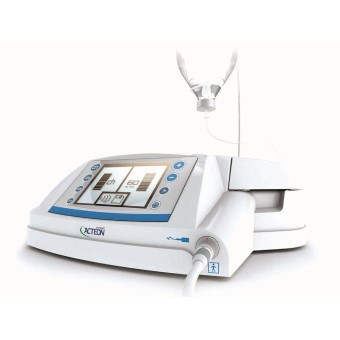

QUY TRÌNH NHỔ RĂNG KHÔN VỚI MÁY SIÊU ÂM PIEZOTOME CÔNG NGHỆ HÀNG ĐẦU CỦA MỸ

Các bác sĩ của Nha khoa Hoa Phương luôn tuân thủ đầy đủ các bước theo quy trình chuẩn dưới đây để đảm bảo giảm tối đa sưng đau và đảm bảo an toàn tuyệt đối cho khách hàng.

Bước 4: Gây tê tại chỗ và tiến hành nhổ răng bằng máy siêu âm piezotome